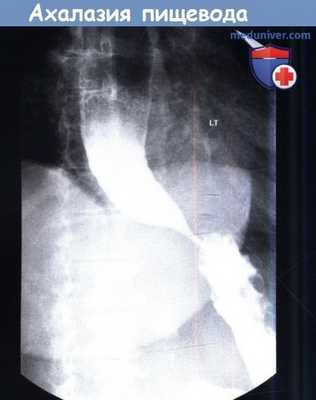

При ахалазии пищевода во время манометрии определяется снижение амплитуды сокращений пищевода менее 30 мм рт. ст., повышение давления нижнего пищеводного сфинктера с нарушением его расслабления. При рентгенографии с барием область нижнего пищеводного сфинктера может быть похожа на птичий клюв, иногда определяется уровень «воздух-жидкость», отсутствие перистальтики. При склеродермии также требуется выполнение рентгенографии с барием. Дряблый, расширенный пищевод похож на пищевод при ахалазии, но нижний пищеводный сфинктер проходим.

Ахалазия с пищеводом в виде «птичьего клюва».